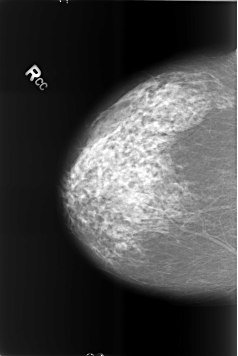

Volume: benign_without_callback_02 Case: B-3427-1

B_3427_1.RIGHT_CC

RIGHT_CC LINES 5696 PIXELS_PER_LINE 3808 BITS_PER_PIXEL 12 RESOLUTION 50 NON_OVERLAY

FILE: B_3427_1.LEFT_CC.OVERLAY

TOTAL_ABNORMALITIES 6

ABNORMALITY 1

LESION_TYPE CALCIFICATION TYPE LARGE_RODLIKE-ROUND_AND_REGULAR DISTRIBUTION REGIONAL

ASSESSMENT 2

SUBTLETY 5

PATHOLOGY BENIGN_WITHOUT_CALLBACK